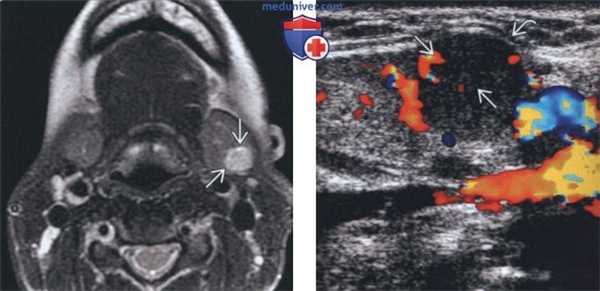

(Слева) На аксиальной МРТ (Т2 ВИ) у молодой женщины с пальпируемым образованием в поднижнечелюстной области в левой ПНЖ визуализируется хорошо отграниченная опухоль овальной формы с гиперинтенсивным сигналом. Признаки распространения опухоли за пределы ПНЖ отсутствуют.

(Справа) На цветовой допплеровской сонограмме у этой же пациентки в левой ПНЖ визуализируется хорошо отграниченное солидное образование, деформирующее наружный контур железы. В образовании не определяются кальцинаты или кистозные изменения, присутствует периферический и внутренний кровоток.